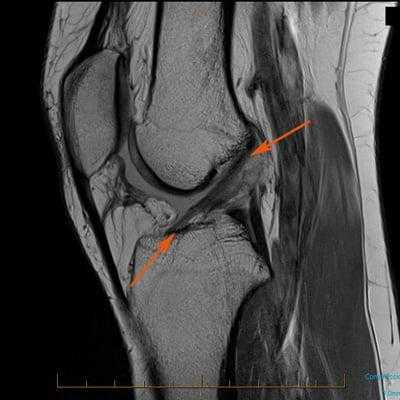

Для обнаружения рубцово-измененной ткани ранее установленного трансплантата ПКС и оценки расположения костных каналов, а также свежих повреждений капсульно-связочного аппарата мы использовали магнитно-резонансную томографию во всех случаях.

Нарушение целостности, а именно ее разрывы, преимущественно происходят на почве спортивных травм, а также в результате падений с зафиксированными параллельно поверхности ногами (травма лыжников), неудачных приземлений после прыжка на выпрямленные ноги. Поражение связочных пучков также может возникнуть из-за сильного удара с тыльной стороны колена, скручивающих и резких движений, например, при крутом повороте или резком торможении в момент бега. Распознать, что произошло поражение именно данной связки, можно только посредством определенных средств диагностики:

- МРТ (КТ и рентген менее эффективны);

Как травма выглядит на МРТ.

Рентгенографию в боковых проекциях проводили стандартно — при максимальном разгибании или под нагрузкой, при небольшом сгибании коленного сустава — для выявления смещения голени кпереди. При этом особое внимание уделяли металлическим фиксаторам (расположение, тип изделия), расположению костных каналов, оценке выраженности дегенеративных изменений и деструкции костных каналов (бедренного, большеберцового).

8. Определение изменений каналов (расширение, формирование кист). Во всех случаях изменения каналов мы определяли с максимальной точностью до ревизии сустава. Диагностическим методом выбора следует считать рентгеновскую компьютерную томографию, так как магнитно-резонансная томография подходит в меньшей степени из-за артефактов от металлических фиксаторов.

Во всех случаях хронической нестабильности была выполнена рентгенография в двух стандартных проекциях.

В боковой проекции можно проверить рентгенологический тест Лахмана. Для этого необходимо выполнить два рентгенографических исследования в положении незначительного сгибания в коленном суставе: первое при расслабленном положении голени, а во время выполнения второго — имитировать тест. Исследование в этой проекции помогает выявить дегенеративные изменения межмыщелкового возвышения (наличие остеофитов), умеренный склероз кортикального слоя заднемедиального участка мыщелка большеберцовой кости, а также определить степень смещения проксимального отдела голени по отношению к бедру. Мы считаем, что смещение на 3—4 мм является нормальным, а смещение до 20 мм — признаком дефицита ПКС, величина которого зависит от состояния периферических связочных структур.